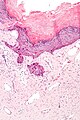

| LM | ectatic superficial dermal vessels with overlying hyperkeratosis (thick stratum corneum); should have "epidermal collarette" (vascular space is surrounded by epidermis on three sides) |

- Ectatic superficial dermal vessels.

- Overlying hyperkeratosis (thick stratum corneum).

- Should have "epidermal collarette".[2]

- Vascular space surrounded by epidermis on three sides.

- Irregular acanthosis.

- Longer rete ridges.